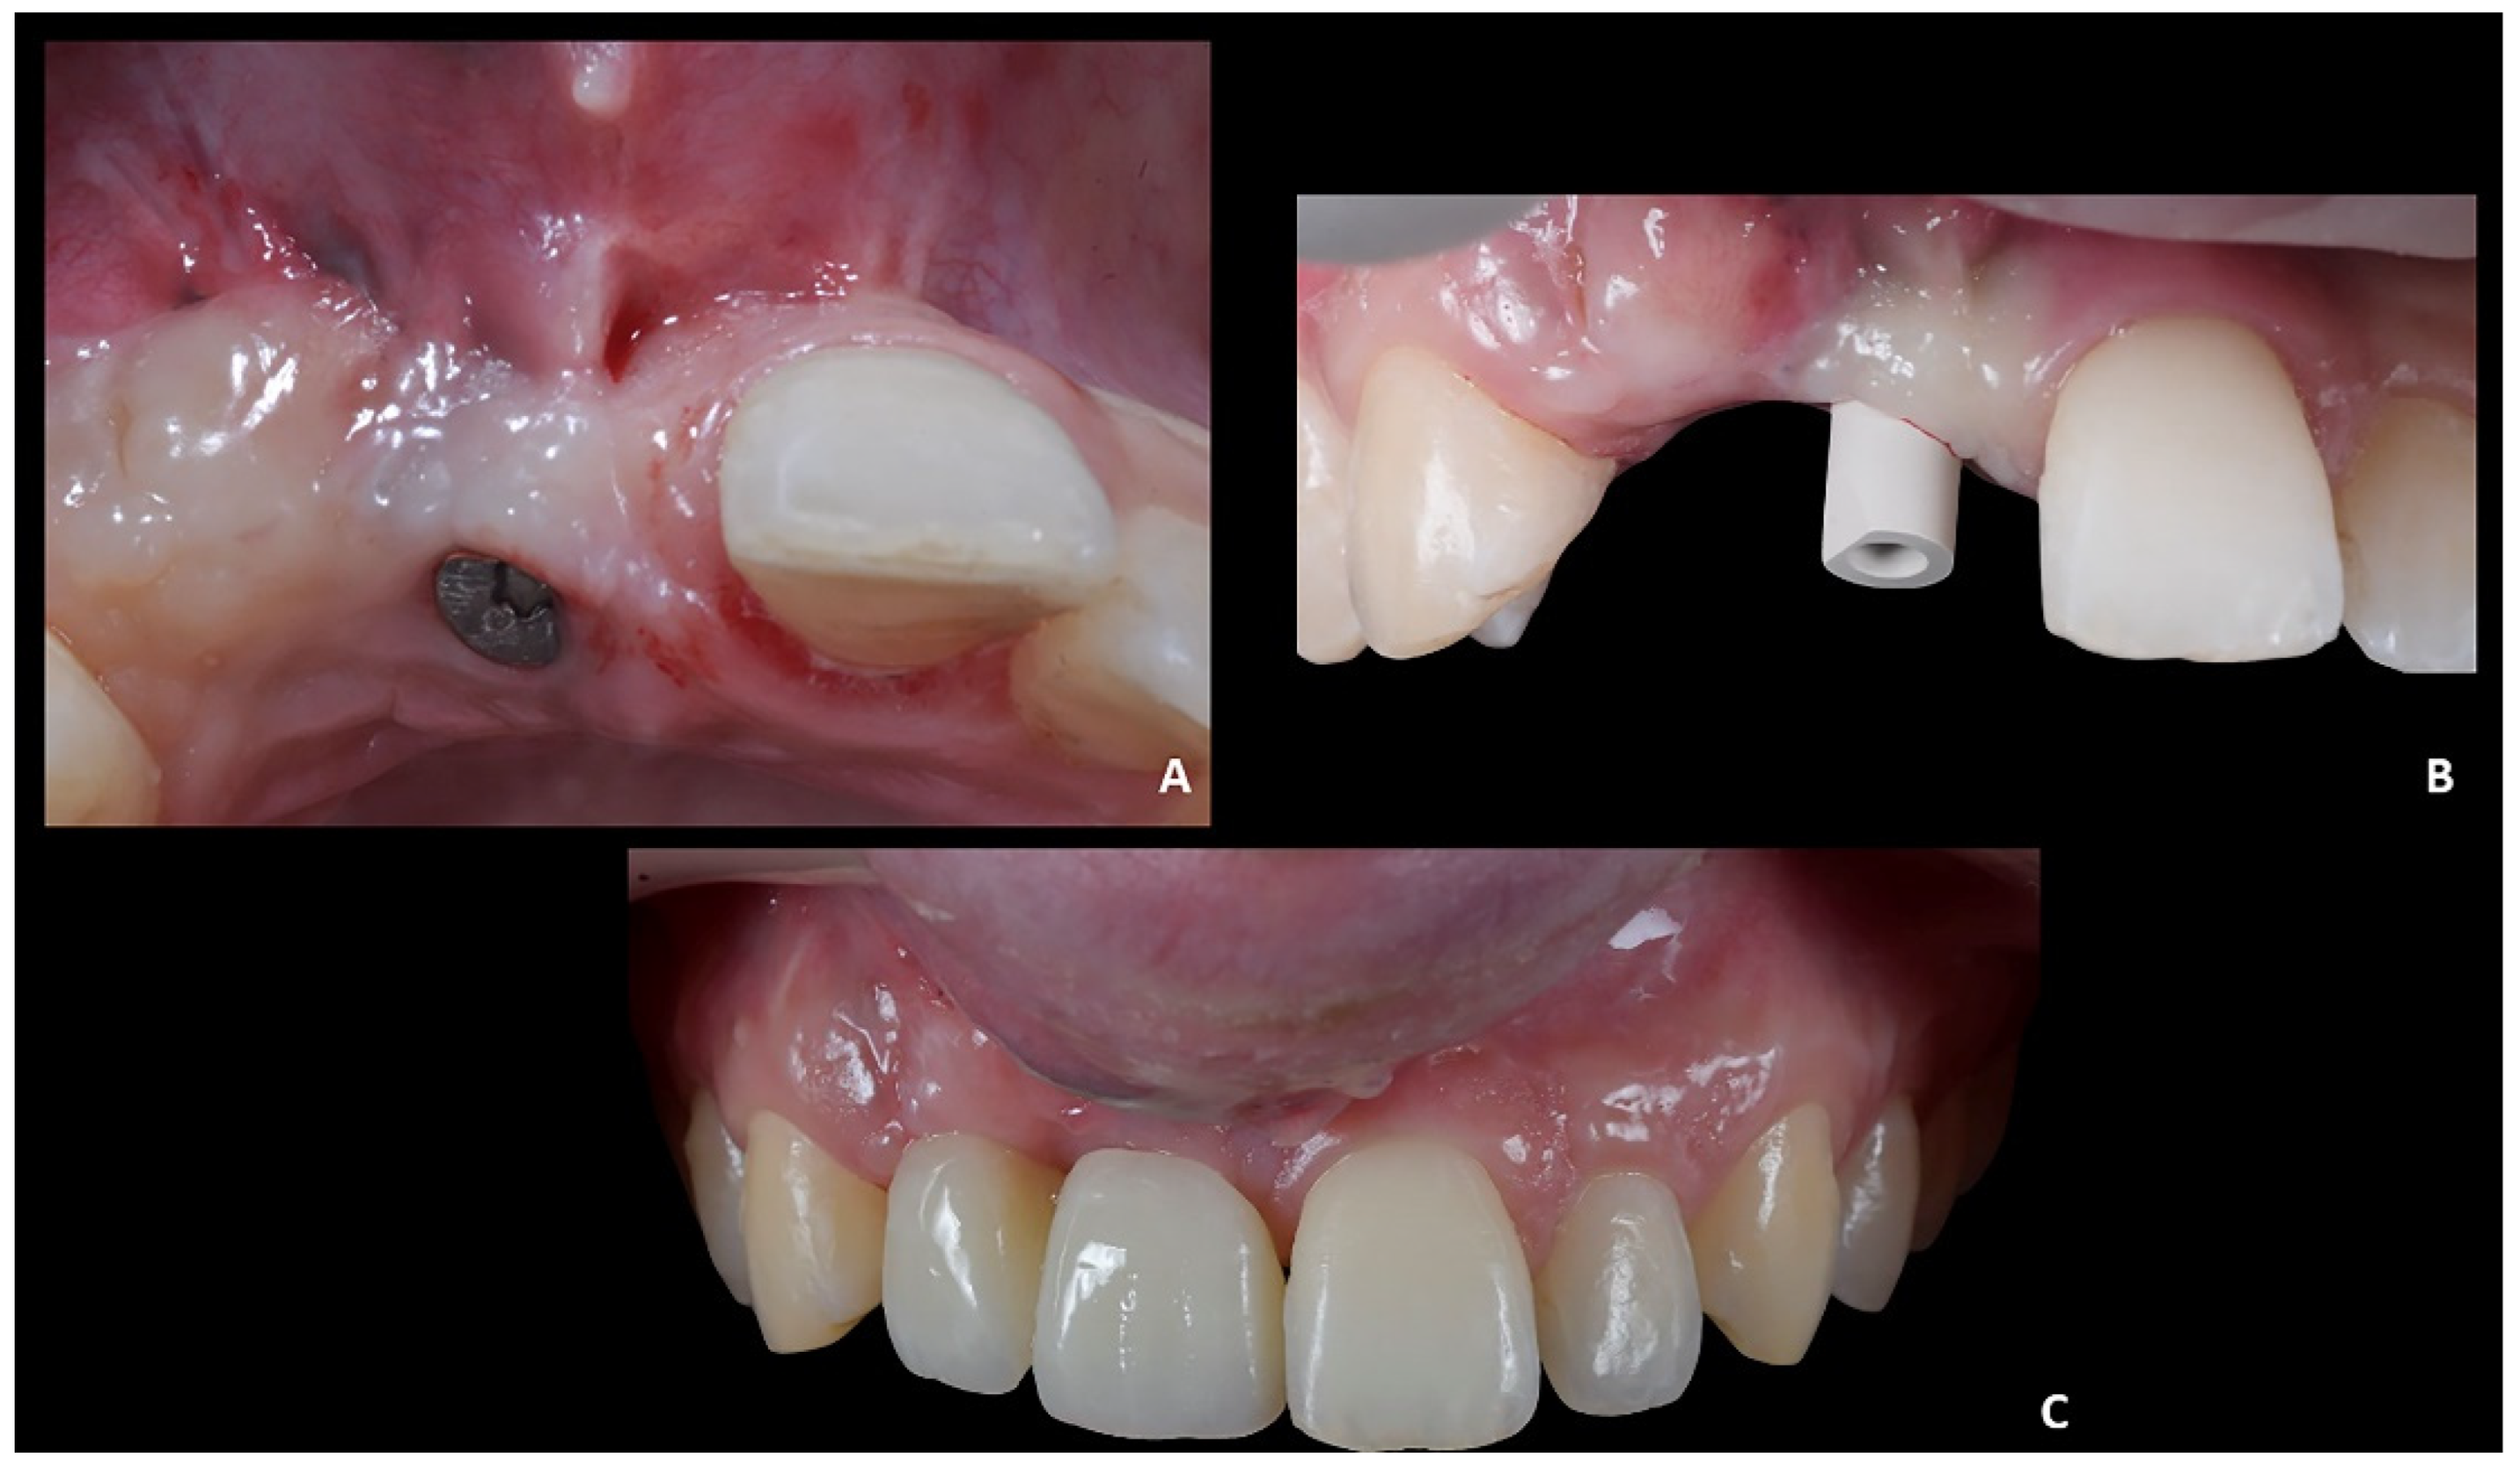

Figure 11. Case 2. (A) Healing abutment; (B) intra-oral scan with scan-body to detect the axial orientation of the implant; (C) prosthetic restoration.

• Prosthetically guided implant planning. After removing the provisional prosthesis, an intra-oral scan was recorded, and the lab technician was asked to produce a virtual wax-up of the ideal position of the teeth. A Cone-Beam Computed Tomography (CBCT) was performed, and the 3D rendered model of the maxilla was registered with the intra-oral scan using the implant planning software Co-Diagnostix (Straumann, Montreal, Canada) (Figure 9). The software was used to plan the implant’s ideal position and design a surgery guide. Figure 10 shows the clinical procedure of the guided implant surgery. Once the osseointegration occurred, an intra-oral scan was performed to register the position of the implant and the surrounding soft tissues with the healing abutment in place (Figure 11A,B).

Positioning of the provisional prosthesis (11 with cantilever 1.2). The scan file was sent to the lab technician, which was asked to design a fixed temporary prosthesis in polymethyl methacrylate (PMMA), screwed onto the implant, and with the following instructions: (1) designing the 1.1 and 1.2 with the same size of contralateral teeth, and (2) maintaining the ideal overjet and overbite ratio compared to opposite arch (Figure 11C).